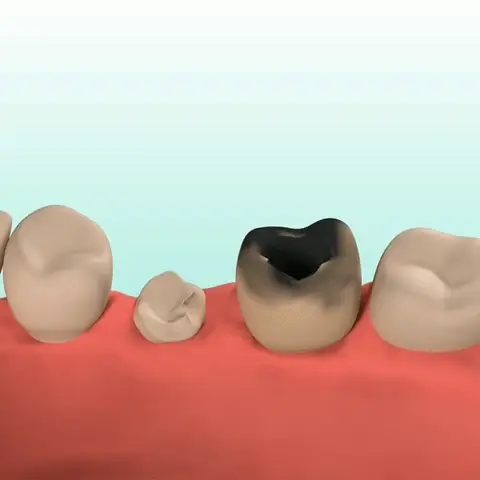

Dental caries develop when germs damage tooth enamel and gradually penetrate into the dentin and even the pulp. This can result in bad breath, toothaches, weakened teeth, and potential tooth loss. The presence of caries often triggers a chain reaction, causing healthy teeth to be affected as germs spread to adjacent teeth.

Prevent Cavities

FURZERO™ Herbal Brightening Oral Repair Foam can help you kill bacteria that penetrate deep into the alveolar and root canal, stimulate the restorative formation of dentin, and help repair tooth decay. For severely necrotic cavities, it can stimulate the gums to produce new tooth germs and promote the growth of new teeth.